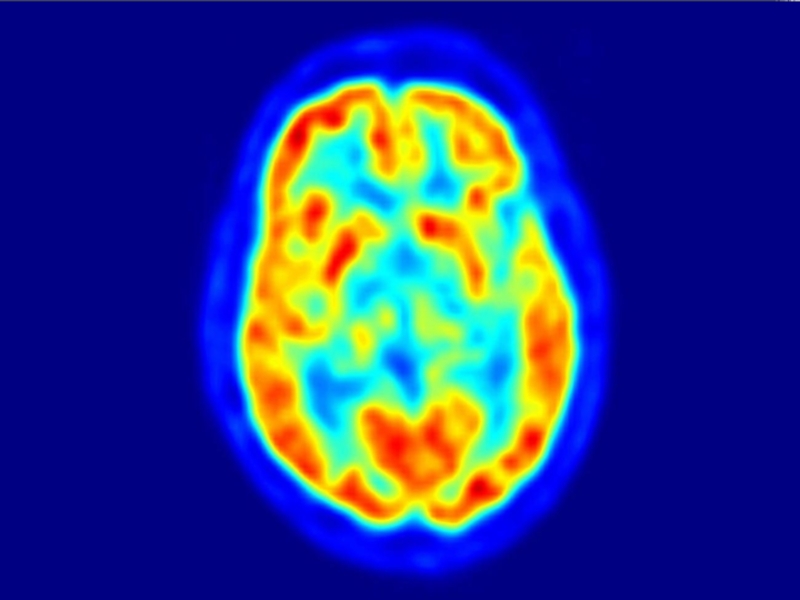

Слайд 16Поражённые органы захватывают препарат наиболее сильно, в их зоне выделяется

большее количество энергии, поэтому на изображении они начинают светиться, таким

образом маркируя проблему.

Процедура проведения (2)

Поражённые органы захватывают препарат наиболее сильно, в их зоне выделяется большее количество энергии, поэтому на изображении они